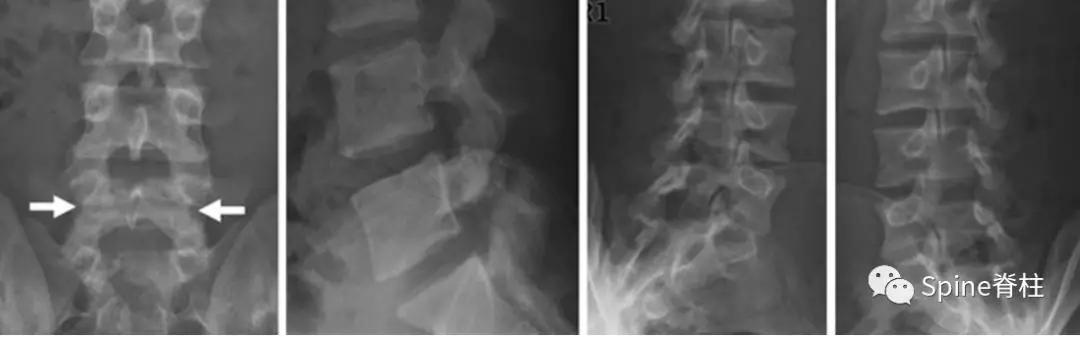

腰椎双斜位片是需要的,通常表现为“ 苏格兰狗脖子”断了(见下图) 。但对于一些隐匿的患者,腰椎双斜位片是看不出的,这时候需要行腰椎CT、MRI进一步明确诊断,少数部分需行核素骨扫描才能明确诊断。

图:箭头所指为苏格兰狗脖子断了

腰椎斜位片上苏格兰狗脖子=腰椎峡部

图:腰椎斜位片,图中黑色箭头所示为峡部裂

图:CT所示峡部裂(长箭头),可别认为是棘突骨折